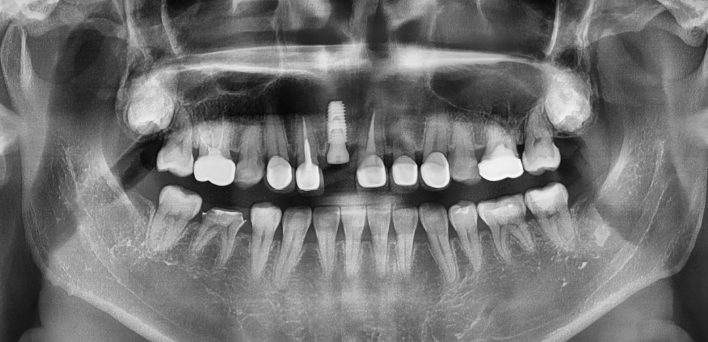

임플란트 : 손 ** 님 (50대)

Before Before

2020.02.30

After After

※ 더서울치과의원은 의료법을 준수하며 위 케이스는 실제 환자의 동의를 얻은 사례로 치료 전, 후가 동일한 환경에서 촬영되었습니다.

환자 케이스에 따라 부작용이 발생할 수 있습니다. 이 부분은 의료진의 충분한 상담과 체크를 통해 예방하고 줄일 수 있습니다.

[임플란트 부작용] 수술 후 관리가 소홀할 경우 출혈, 주위염 등의 부작용이 발생할 수 있어 구강 위생을 철저히 유지하고, 정기적인 검진을 통해 상태를 점검하는 것이 중요합니다.

환자 특징

환자 특징01무치악 상태

환자 특징02수년간 무치악으로 지내심

임플란트가 불가능할것이라

생각하고 내원

위, 아래 6개씩 식립

디지털 풀아치 임플란트

임플란트 Before & After

The seoul dental clinic